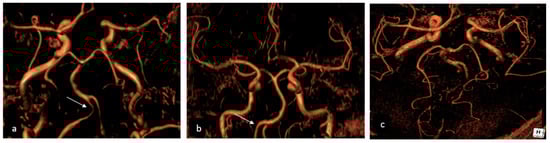

More frequently, HVs are observed in patients with PRES and ischemic stroke, suggesting that they may not only serve as a useful marker of RCVS but may also indicate clinical severity. HVs are distinct from subarachnoid hemorrhage, as they do not appear hypointense on SWI sequences [72]. Vasospasm, on the other hand, can be visualized with magnetic resonance angiography (MRA) or through computed tomography angiography (CTA) (as shown on Figure 3) when it starts involving larger cerebral vessels. As a result, the diagnosis could be challenging in the acute phase and often delayed. In cases of treatment-related RCVS, cerebral edema is more frequently observed and vasoconstriction is more widespread and severe compared to the idiopathic form where vasoconstriction is usually segmental.

6.2. Catheter Angiography

The diagnostic gold standard remains digital subtraction angiography. During angiography, smooth tapered narrowing followed by abnormal dilated segments can be visualized. This alternation of narrowing and dilatations is responsible for the typical “sausage on strings” appearance [75]. Angiography also allows for the exclusion of alternative diagnoses and the study of vasospasm reversibility through intra-arterial administration of vasodilators [36]. This is particularly useful because the diagnosis of RCVS is often made retrospectively once the reversible nature of vasospasm is demonstrated. Being able to assert early in the disease process that vasospasm is reversible significantly advances the diagnosis and enables more informed patient monitoring. In fact, in up to a third of cases, angiographic evaluation is normal within the first week of symptom onset due to centripetally proceeding vasospasm [76].

Finally, normalization of angiographic findings is typically observed within 8–12 weeks. However, the evolution of cerebral vasospasm is not uniform; so, while some vessels improve, others worsen during the monitoring period [76].

Figure 3. A 58-year-old female admitted to the Emergency Department due to thunderclap headache, diagnosed with RCVS. (a) The initial Angio CT showed bilateral V4 vasoconstriction (arrow) and narrowing posterior cerebral arteries; (b) three months later, the follow-up Angio CT showed complete resolution of vertebral artery vasoconstriction (arrows); (c) the follow-up imaging also showed complete recanalization of posterior cerebral arteries. RCVS: reversible cerebral vasoconstriction syndrome.